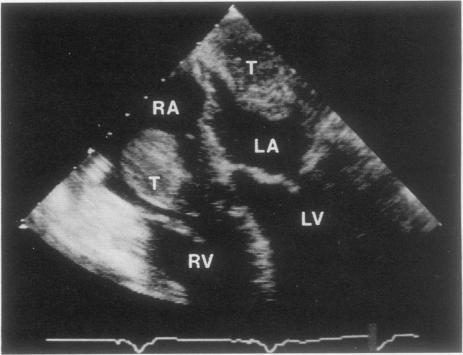

Transesophageal echocardiography and 2-dimensional transthoracic echocardiography have proved to be extremely valuable in the diagnosis of cardiac masses. In this report, we review the echocardiographic findings, clinical history, and histopathologic findings in 21 patients with intracardiac masses who underwent transthoracic echocardiography, transesophageal echocardiography, or both, at our institution. Of these patients, 14 had benign masses and 7 had malignant tumors. The potential role of transesophageal echocardiography in the diagnosis and treatment of patients with intracardiac masses is discussed. We believe that transesophageal echocardiography offers the cardiologist and cardiovascular surgeon the capability of more accurate preoperative and intraoperative assessment of cardiac masses.

经食管超声心动图和二维经胸超声心动图已被证明在心脏肿物的诊断中极具价值。在本报告中,我们回顾了在我院接受经胸超声心动图、经食管超声心动图或两者检查的21例心内肿物患者的超声心动图表现、临床病史及组织病理学发现。这些患者中,14例为良性肿物,7例为恶性肿瘤。讨论了经食管超声心动图在心脏肿物患者诊断和治疗中的潜在作用。我们认为经食管超声心动图为心脏病专家和心血管外科医生提供了更准确地进行心脏肿物术前和术中评估的能力。